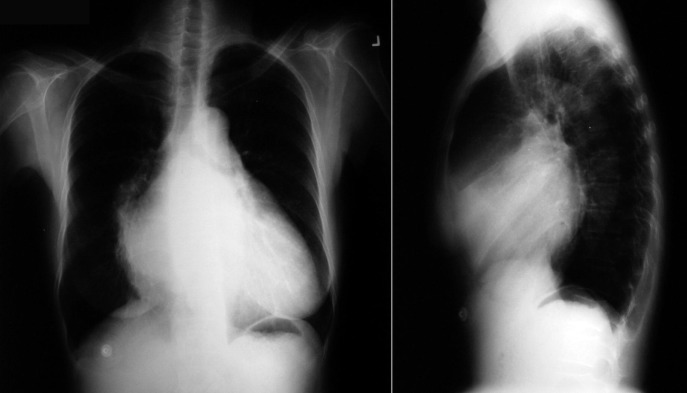

The radiographic findings of mitral stenosis ( Graphic 15-1 ; Figs. 15-1 to 15-16 ) reflect the pressure overload of the left atrium and pulmonary veins, and later of the right heart. As well, the commonly associated chronic atrial fibrillation contributes to (bi)atrial dilation. Associated rheumatic valvular lesions such as mitral regurgitation, tricuspid regurgitation, aortic insufficiency, and aortic stenosis/aortic insufficiency are common, and they alter the appearance of the heart.